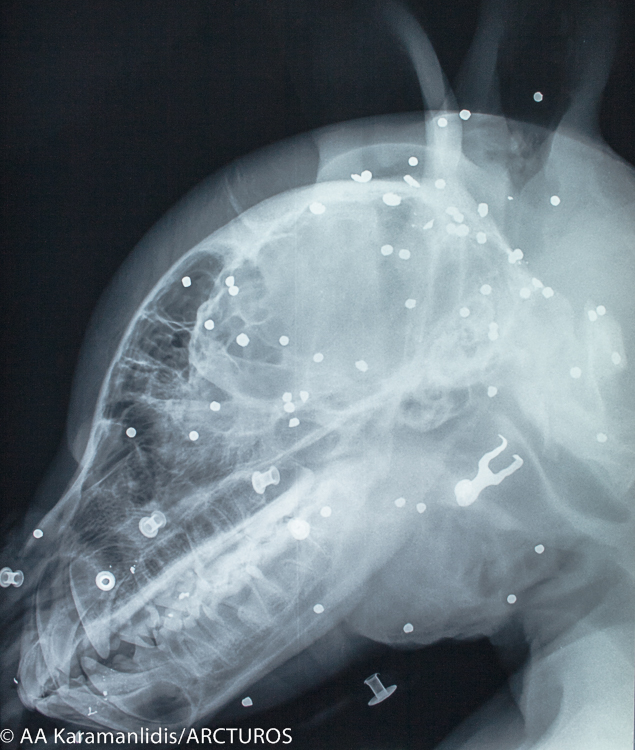

Ο “Γιώργος” μεταφέρθηκε, την Τρίτη, από την Ομάδα Άμεσης Επέμβασης του Αρκτούρου στη Μονάδα Εξωτικών και Άγριων Ζώων και στη Μονάδα Αναισθησιολογίας και Εντατικής Θεραπείας της Κτηνιατρική Σχολής του ΑΠΘ για τις απαραίτητες εξετάσεις. Έπειτα από κλινική εξέταση και τη λήψη ακτινογραφιών διαπιστώθηκε κρανιοεγκεφαλική κάκωση, ενώ παράλληλα βρέθηκαν και άφθονα βλήματα πυροβόλου όπλου στην περιοχή της κεφαλής και του θώρακα.